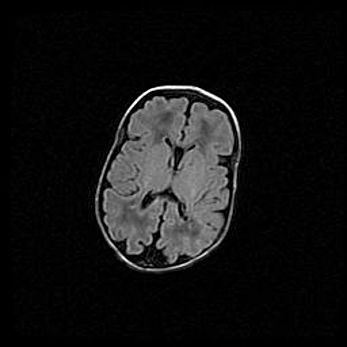

Множественные кисты обоих полушарий головного мозга, наибольшая из них в правой затылочной области. Ассиметричная атрофическая гидроцефалия.

Возраст: 7 месяцев

Вес: 5660 г

Пол: мужской

Окружность головы: 41,5 см

Срок гестации: 28-29 недель

Кисты головного мозга развиваются в результате многоочаговых некрозов вещества мозга и возникают вследствие перенесенной перинатальной инфекции, менингитов, энцефалитов, асфиксии, родовой травмы, расстройств мозгового кровообращения различного генеза. Образованию кист в веществе головного мозга плодов и новорожденных способствуют такие факторы, как высокое содержание в нем воды, недостаточная (или отсутствие) миелинизация и слабая астроглиальная реакция на повреждение.

Кисты могут сочетаться с гидроцефалией и другими поражениями головного мозга.